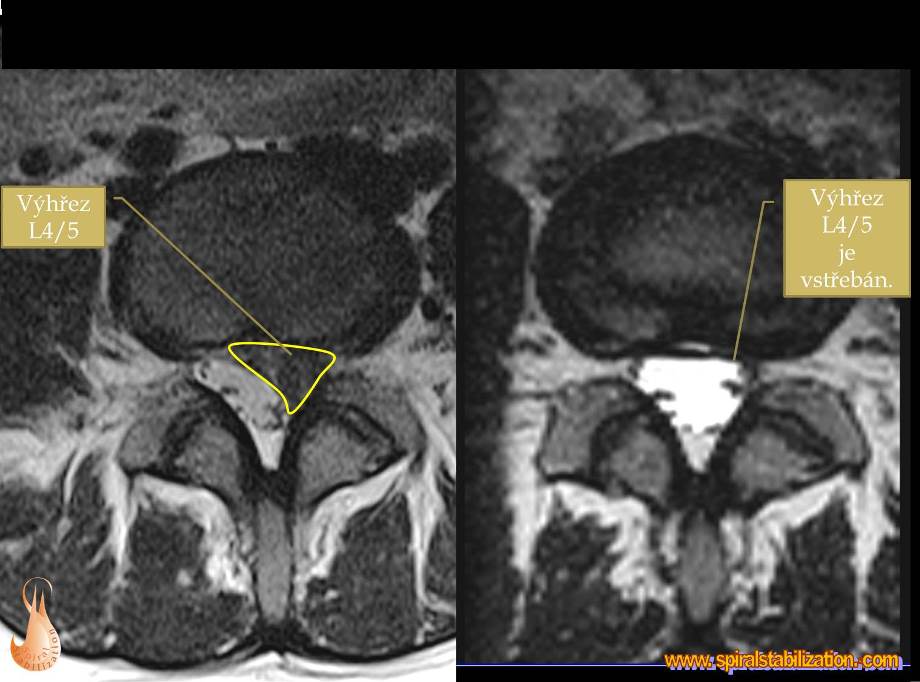

Výsledky hernia L4/L5